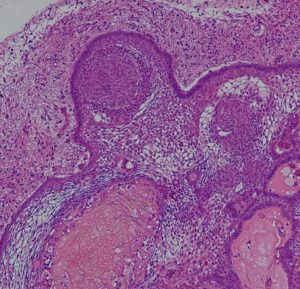

成人の第3脳室内部に局在する頭蓋咽頭腫です。経脳梁法で両側のモンロー孔から全摘出しました。下垂体組織は残っています。これは乳頭状頭蓋咽頭腫と呼ばれるもので,成人にしか発生しません,のう胞がなく石灰化もないのが大きな特徴です。境界が明瞭で柔らかく摘出が簡単なタイプとして知られています。この患者さんも術後に下垂体機能不全も視床下部障害も生じませんでした。

Monomorphous mass of well-differenciated squamous epithelium lacking surface maturation and wet keratin.